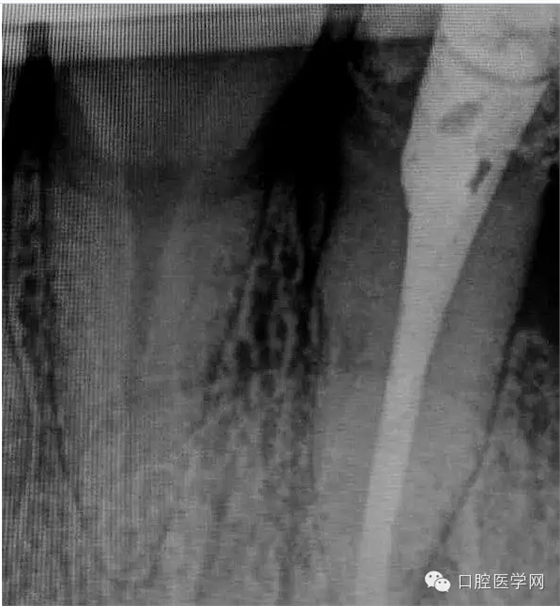

4.準(zhǔn)備放置橡皮障(由于拍片是較遠(yuǎn),所以,橡皮章暫時(shí)取下),去除暫封材料。在顯微鏡放大視野中,蔣調(diào)拌好MTA輸送至根尖部。

5.待MTA凝固后進(jìn)行熱牙膠充填。

一年前接診的病例,在各級(jí)門診診所轉(zhuǎn)診三次,不見好轉(zhuǎn)。最后到本院 !觀察一年以后的效果!